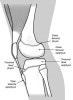

오스굿 슐라터병(오스굿씨병)은 운동시 슬개건의 갑작스런 혹은 지속적인 견인으로, 혀모양의 경골 결절 골단이 부분적으로 분리된 것을 말하여 성장이 왕성한 청소견 시기에 비교적 흔히 경험되는 질환입니다.

초기에는 경골 골절 골단선은 불규칙하게 분리되어 있으나, 말기에는 경골 결절의 세분화가 두드러지게 되며 간혹 슬개건 내에 석회화가 나타나기도 합니다.

한편, 경골 결절이 완전히 떨어진 경우에는 골편이 상방으로 회전 전위되기도 합니다.